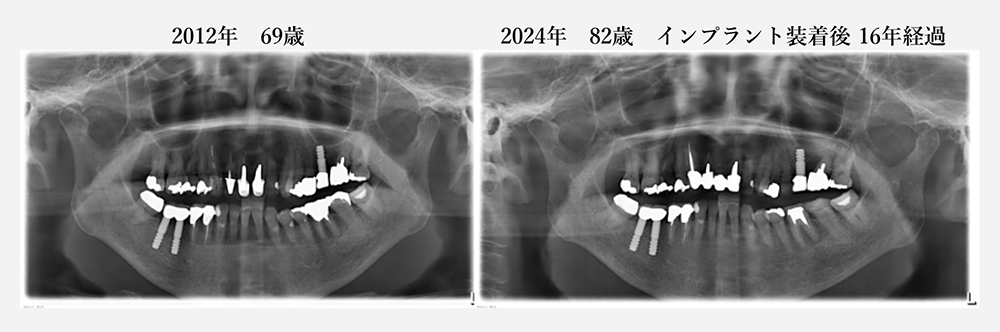

当院で20年以上メインテナンスをしていて、歯を抜くこともなく、

80歳を過ぎてもご自分の歯で美味しく食事ができています。

(デジタルレントゲン導入(2011年)後のレントゲン写真のみとなります)

現在82歳の女性